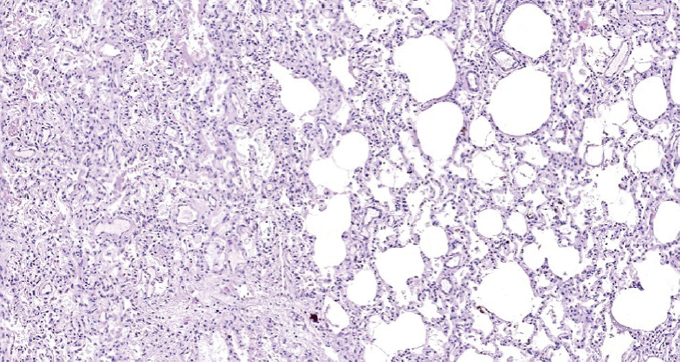

Children get sick less often than adults with a new coronavirus infection (in the Russian Federation, they account for 7.6% of registered cases of COVID-19), with less severe clinical symptoms, they require hospitalization less often, their disease is milder. The frequency of severe and extremely severe cases of COVID-19 in children does not exceed 1%. A clinical case of the course of COVID-19 in a child aged 2 years 4 months is presented. with acute lymphoblastic leukemia. A feature of the presented case is the development of an extremely severe new coronavirus infection in a child with secondary immunodeficiency caused by a long-term course of malignant, treatment-resistant of acute lymphoblastic leukemia. Slow, within 3 months, the development of the infectious process with long-term preservation of normal indicators of the function of the respiratory system led to the formation of viral-bacterial pneumonia with the development of respiratory distress syndrome. Despite the modern complex of therapeutic measures, severe comorbidity led to the development of DIC and multiple organ failure, which was the direct cause of the child’s death. A possible therapy strategy is discussed in a patient with severe comorbidity against the background of secondary immunodeficiency and long-term persistence of SARS-CoV-2 in the presence of IgG antibodies to SARS-CoV-2 in the blood. For the first time, data on morphological changes in the lungs with a long course of COVID-19 (more than 100 days) in a young child are presented.